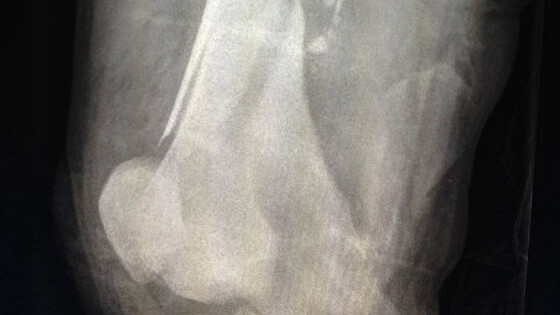

Инженеры смоделировали вытекание крови из простреленной ноги

Инженеры из Калифорнийского университета в Лос-Анджелесе создали компьютерную модель, впервые показывающую, каким образом кровь истекает из раненой ноги человека. Результаты своих исследований авторы доложили на секционном заседании Американского физического общества, а кратко о них сообщает издание New Scientist. В своей работе инженеры для имитации кровоизлияния в поврежденной части человеческого тела использовали гидродинамику сглаженных частиц. Для этого с учетом необходимых анатомических особенностей (расположения костей, мышц, сосудов и кожи) исследователи провели трехмерную реконструкцию человеческой ноги. На примере деформированной баллистическим снарядом человеческой ноги специалисты изучили процессы внутреннего и внешнего кровоизлияний. Инженеры рассмотрели два сценария ранения: в первом случае нога человека расположена вертикально, тогда как во втором случае она расположена горизонтально. Инженеры полагают, что их исследование впервые моделирует процессы, происходящие с кровеносной системой человека при его ранении. Свои наработки авторы собираются использовать в образовательных целях для студентов-медиков, а также для онлайн-консультаций с военными и врачами при возникновении чрезвычайных ситуаций.